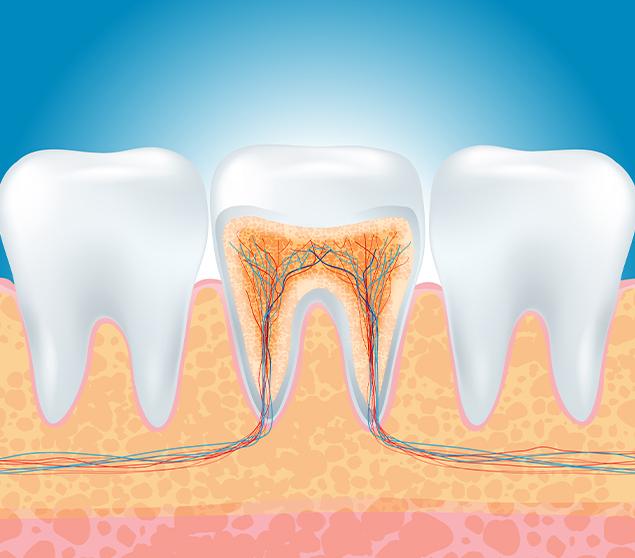

A diseased inner tooth can lead to pain, sensitivity, and the development of infection. In some cases, abscess formation may occur if infection progresses.